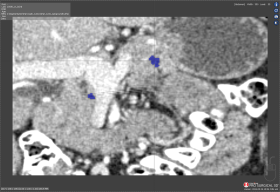

Scan 30: Bleed of 46,932

Bleed

Bleed is the area of the Test segmentation that covers area outside of the Ground truth segmentation.